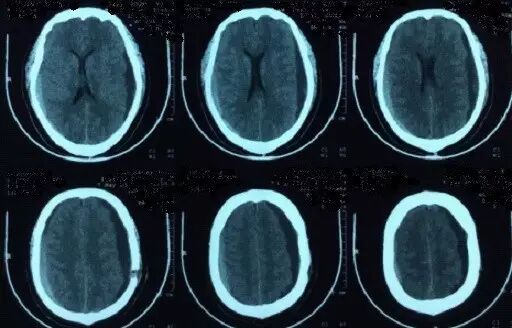

2017年5月7日上海某医院头颅CT提示:颅脑术后,双侧额颞顶部硬膜下积液积血(图4)。于2017年5月9日行双侧钻孔引流术,2017年5月12日头颅CT提示:钻孔术后改变,颅内积气(图5)。患者术后头痛症状持续加重,出现意识不清,5月15日再次复查头颅CT提示脑肿胀明显(图6),于5月17日再次行右侧硬膜下血肿清除+左侧硬膜下血肿钻孔引流术,术后患者出现脑疝,于2017年5月21日行右侧额颞顶扩大去骨瓣减压术+血肿清除术。(图7)

图6. 2017年5月15日头颅CT显示脑沟脑池不清晰,脑肿胀明显。

图7. 2017年5月22日外院头颅CT提示:右侧额颞顶部去骨瓣术后改变。

图8. 2017年7月4日本院头颅CT提示:右侧额颞顶部去骨瓣术后改变,脑室扩张。